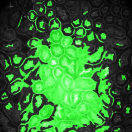

The first row in Figure 3 displays an original microscopy image (), its inhomogeneity corrected version (), and manually delineated groundtruth (), respectively. For brevity we have omitted the superscript in the notation. The second row shows segmentation results of various 3D methods such as 3D region-based active contours [10] (3Dac), 3D active contours with inhomogeneity correction [11] (3DacIC), and 3D Squassh presented in [12] (3Dsquassh). Similarly, the third row portrays various segmentation methods particularly designed for tubular structure segmentation such as ellipse fitting method presented in [15] (Ellipse Fitting), the Jelly filling method in [20] (Jelly Filling), and tubule segmentation using steerable filter [21] (Steerable Filter). Finally, the last row shows segmentation results of our proposed CNN architecture without inhomogeneity correction [27] (2DCNN) and with inhomogeneity correction (2DCNNIC).

For visual comparison we highlighted groundtruth regions in red, segmented tubule regions in green, and background in black. As observed in Figure 3, our proposed method appeared to perform better than the other six methods shown in the second and third rows by distinguishing tubules and was similar performance to 2DCNN. Note that since some methods such as Ellipse Fitting, Jelly Filling, and Steerable Filter only segmented boundaries of tubule structures, tubule interiors were filled in order to perform a fair comparison using connected components with a -neighborhood systems. Also, based on the assumption that tubule regions should contain lumen, if a filled region contained lumen pixel, the region was identified as a tubule region. However, if a filled region did not contain any lumen pixels, the region was considered as a background region.

The segmentation results shown in the second row generally missed many tubule regions. More specifically, 3Dac and 3Dsquassh could not capture the tubular structures but captured some in the center regions due to the intensity inhomogeneity of microscopy images. 3DacIC failed to segment tubular structures but captured multiple lumens inside tubules as well as some tubule boundaries. In contrast, the segmentation results displayed in the third row showed falsely detected tubules. The main reason is that these tubule segmentation methods focused only on detecting boundaries of tubular structures. In particular, due to weak/blurry edges of fluorescence microscopy images, many boundaries were not continuous causing the filling operation to overflow from one tubule to another or to the background regions. The segmentation results using the CNN generally successfully segmented and identified each tubule region.

Figure 4 provides an alternative way to show the segmentation results. In particular, yellow regions correspond to true positives which are pixel locations that are identified as tubules in both the groundtruth and segmentation results. Green regions correspond to false positives which are pixel locations that are identified as background in groundtruth but tubules in segmentation results. Similarly, red pixels correspond to false negatives, namely pixel locations identified as tubules in the groundtruth but background in segmentation results, and black pixel regions correspond to true negative that are identified as background in both groundtruth and segmentation results. The green regions indicate Type-I error (false alarm) regions and the red regions represent Type-II error (miss) regions. As observed from Figure 4, the segmentation results in the first row contained large red regions which mean large regions of tubules were missed. Conversely, the segmentation results shown in the second row contained many green regions indicating many background regions were falsely segmented as tubule regions. In contrast, the segmentation results in the third row had reasonably small green regions and red regions which indicate that the deep learning based segmentation results had higher pixel accuracy with relatively low Type-I and Type-II errors.